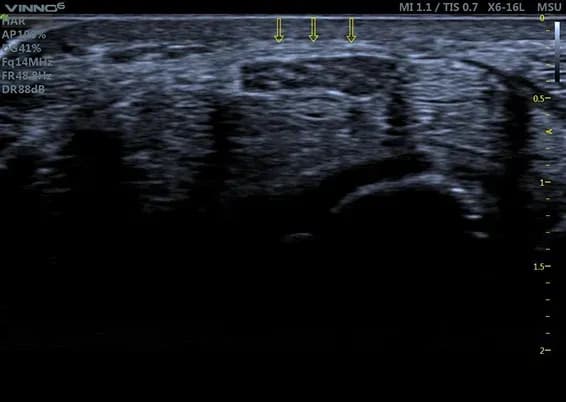

Kalkschulter

Die Kuppelförmige Kalkansammlung in der Supraspinatussehne ist so dicht, dass die darunter liegende Knochenoberfläche der Oberarmkopfes unterbrochen scheint. Dieses Phänomen nennen wir Schallschatten und sagt etwas über die Ausprägung der Verkalkung aus.